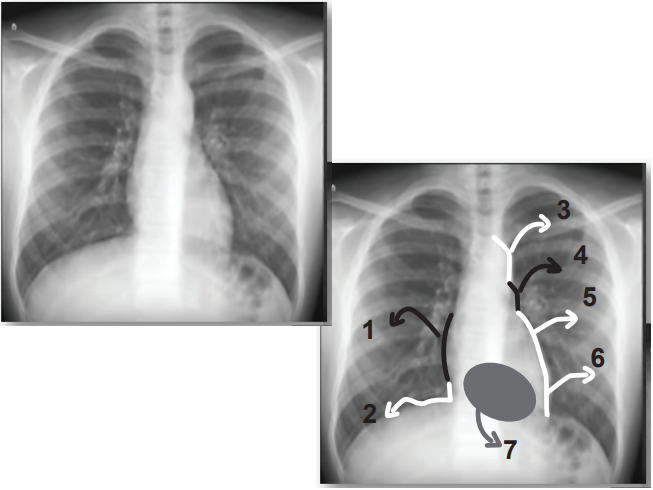

Você preparou uma prova de radiografia de tórax para os seus alunos de biomedicina. Para tanto, escolheu uma radiografia normal de tórax (póstero anterior) de um adulto jovem, e em seguida identificou estruturas de 1 a 7, conforme abaixo, para que o aluno identificasse os contornos da silhueta cardíaca. Seguem as respostas de cinco alunos. Assinale a alternativa do aluno que acertou todas as estruturas:

ALUNOS | 1 | 2 | 3 | 4 | 5 | 6 | 7 |

Mateus | veia cava superior | ventrículo direito | carótida | veia pulmonar | átrio esquerdo | ventrículo esquerdo | ápice do ventrículo esquerdo |

| Lucas | ventrículo direito | ventrículo direito | carótida | aorta | veia pulmonar | ventrículo direito | ápice do ventrículo esquerdo |

| Beth | veia cava inferior | junção com a veia cava inferior | aorta | tronco da veia pulmonar | átrio esquerdo | ventrículo esquerdo | ventrículo direito |

| Julia | átrio direito | junção com a veia cava inferior | aorta | tronco da artéria pulmonar | átrio esquerdo | ventrículo esquerdo | ventrículo direito |

| Daniel | átrio direito | ventrículo direito | carótida | aorta | ventrículo esquerdo | ventrículo esquerdo | ápice do ventrículo esquerdo |